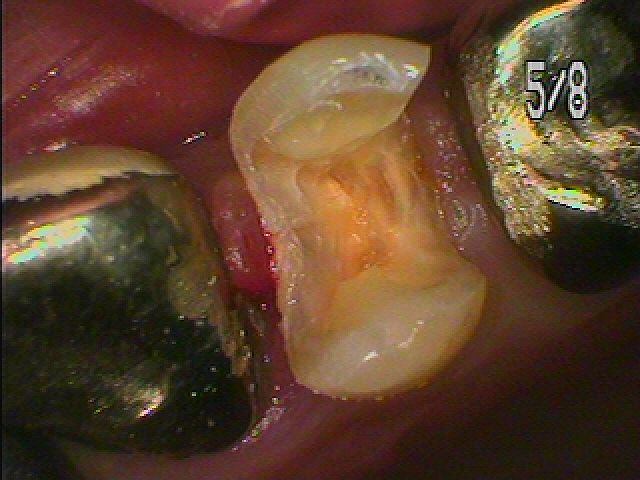

銀歯をはずして虫歯治療 白いセラミックへ鑓変えていきます|お知らせ |広島市安佐南区の歯科医院 銀歯をはずして虫歯治療 白いセラミックへ鑓変えていきます トップ お知らせ・ブログ お知らせ 銀歯をはずして虫歯治療 白いセラミックへ鑓変えていきます 銀歯をはずして虫歯治療 白いセラミックへ鑓変えていきます 左上4番の銀歯をはずしていきます 銀歯をはずした直後になります 中は痛んでいるようです 虫歯が見えてきました 神経に気を付けながら虫歯を除去してCR樹脂にて覆罩を行い、 型取りを行っていきます セレックセラミックにて修復していきます このようにきれいなセラミックが入りました Web診療予約 初めての方へ 選ばれ続ける理由 院内設備について 歯が痛いしみる一般歯科 歯がぐらぐらする歯周病 健康な歯を保ちたい予防歯科 子供の虫歯予防をしたい小児歯科 銀歯をセラミックに審美歯科 白い歯を目指しませんか?ホワイトニング 矯正専門医がいるので安心矯正歯科 抜けた歯を補いたいインプラント・入れ歯 医院案内 スタッフ紹介 メリィハウス歯科クリニックオフィシャルホームページ ラベンダー歯科クリニックオフィシャルホームページ お知らせ・ブログ ホーム 診療科目 一般歯科 歯周病治療 予防治療 小児歯科 審美治療 ホワイトニング 矯正歯科 入れ歯・インプラント マウスピース矯正 初めての方へ 院長・スタッフ 設備紹介 医院案内・アクセス メニューを閉じる